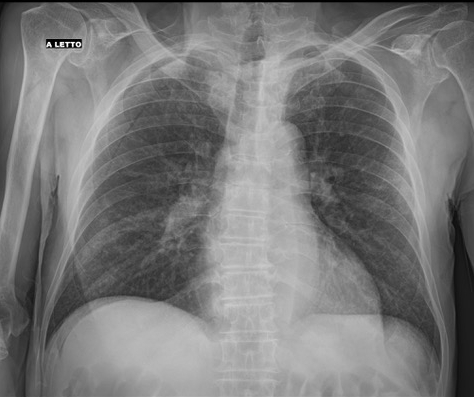

57-year-old male

patient admitted to the ED with fever, cough and...